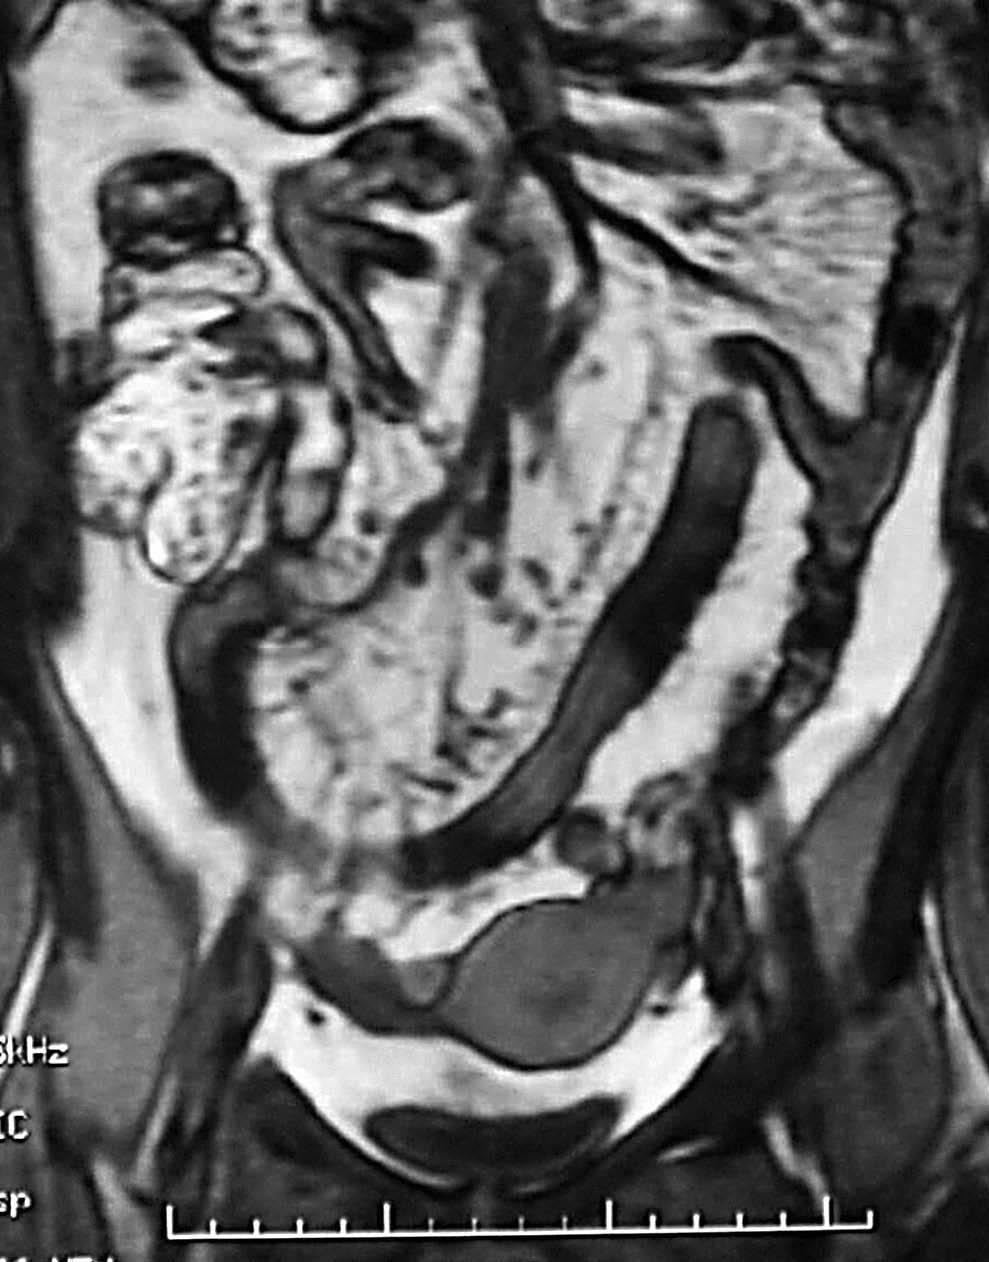

Los hallazgos en la TC y la RM sugestivos de EC en fase activa son la hiperemia, característica de un proceso inflamatorio y la estratificación de la pared intestinal (fig. 8). El concepto de hiperemia que depende de la prominencia, tortuosidad y dila-tación de los vasa recta, se traduce por el signo del "peine" (fig. 9), descrito por Meyers y McGuire16 en estudios tomodensitométricos de pacientes en fase activa de la EC. Si bien no es un signo patognomónico de la EC, la hiperemia a nivel de las asas intestinales es marcador de actividad17. La estratificación de la pared intestinal justifica un aspecto en "diana" (fig. 3B) con una zona de alto valor de atenuación interna que corresponde a la mucosa, otra zona también de alto valor de atenuación periférica que corresponde a la muscular-serosa y una zona intermedia entre ambas, de menor valor de atenuación que corresponde a la submucosa edematosa en relación con la ectasia linfática12.

En este suptipo (fig. 10) hay también un proceso inflamatorio activo y aparece estriación de la grasa mesentérica en relación con edema e inflamación, pero las ulceraciones fisurantes se hacen más profundas (úlceras en "espina de rosal"). Estas ulceraciones penetrantes van a ser la base de las futuras fístulas y también de las complicaciones extraluminales, como pueden ser abscesos o masas inflamatorias.

Fig. 9.--Enfermedad de Crohn, fase activa inflamatoria. (A) El signo del peine en la resonancia magnética (RM), secuencia potenciada en T1, imagen de orientación coronal. (B) Secuencia potenciada en T2, corte coronal, muestra prominencia y dilatación de los vasa recta.